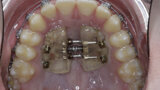

New Age orthodontics and orthopaedics with temporary anchorage devices